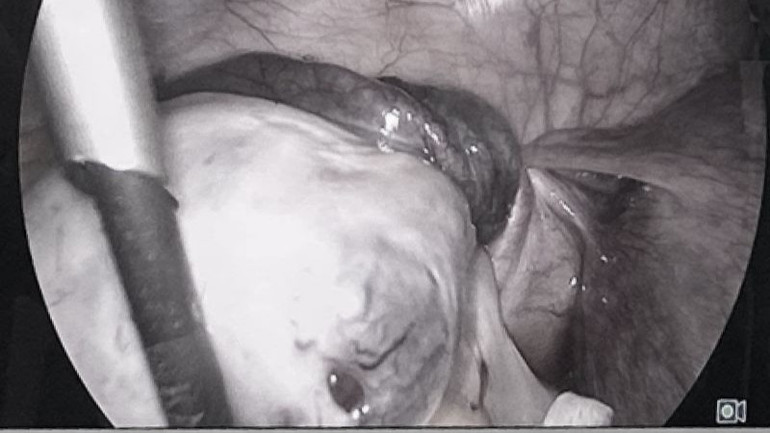

Nhận định tình trạng nguy hiểm, bệnh nhân được kịp thời phẫu thuật nội soi cấp cứu tháo xoắn và bóc u bì buồng trứng trái.

| Hình ảnh u xoắn buồng trứng. |

Bác sĩ chuyên khoa II Nguyễn Văn Thưởng, chuyên khoa Ngoại, Bệnh viện Đa khoa Medlatec - bác sĩ trực tiếp thực hiện ca phẫu thuật cho bệnh nhân chia sẻ, ca phẫu thuật được thực hiện với phụ nữ mang thai lần đầu và trẻ tuổi nên cần ưu tiên bảo tồn buồng trứng cũng như bảo vệ thai nhi. Quá trình phẫu thuật mặc dù vòi tử cung tím đen nhưng khi tháo xoắn đã hồng hào trở lại.

Ca phẫu thuật diễn ra thuận lợi, bác sĩ lấy toàn bộ vỏ u bì và tổ chức trong u (lông, tóc, xương, móng, răng - những thành phần của thời kỳ phôi thai còn sót lại), bảo tồn hoàn toàn vòi trứng và buồng trứng trái.